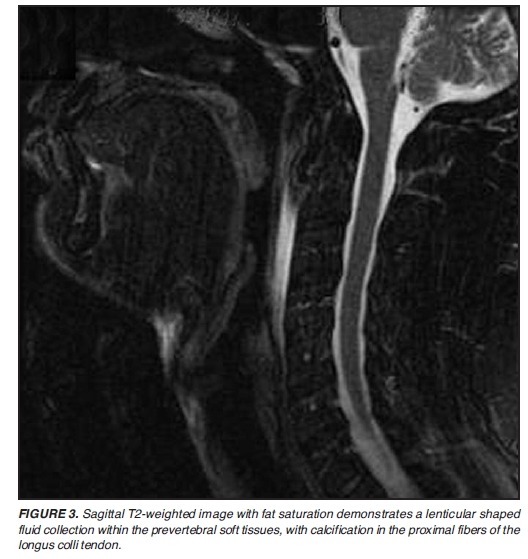

드물지만 neck pain 통찰하는데 중요한 질환 longus colli tendinitis

흉쇄유돌근과 함께 tendinitis가 발생한다. 심지어 calcific tendinitis까지.

첨부파일 Acute calcific tendinitis of the longus colli muscle.pdf

첨부파일 Acute calcific prevertebral tendonitis of longus colli.pdf